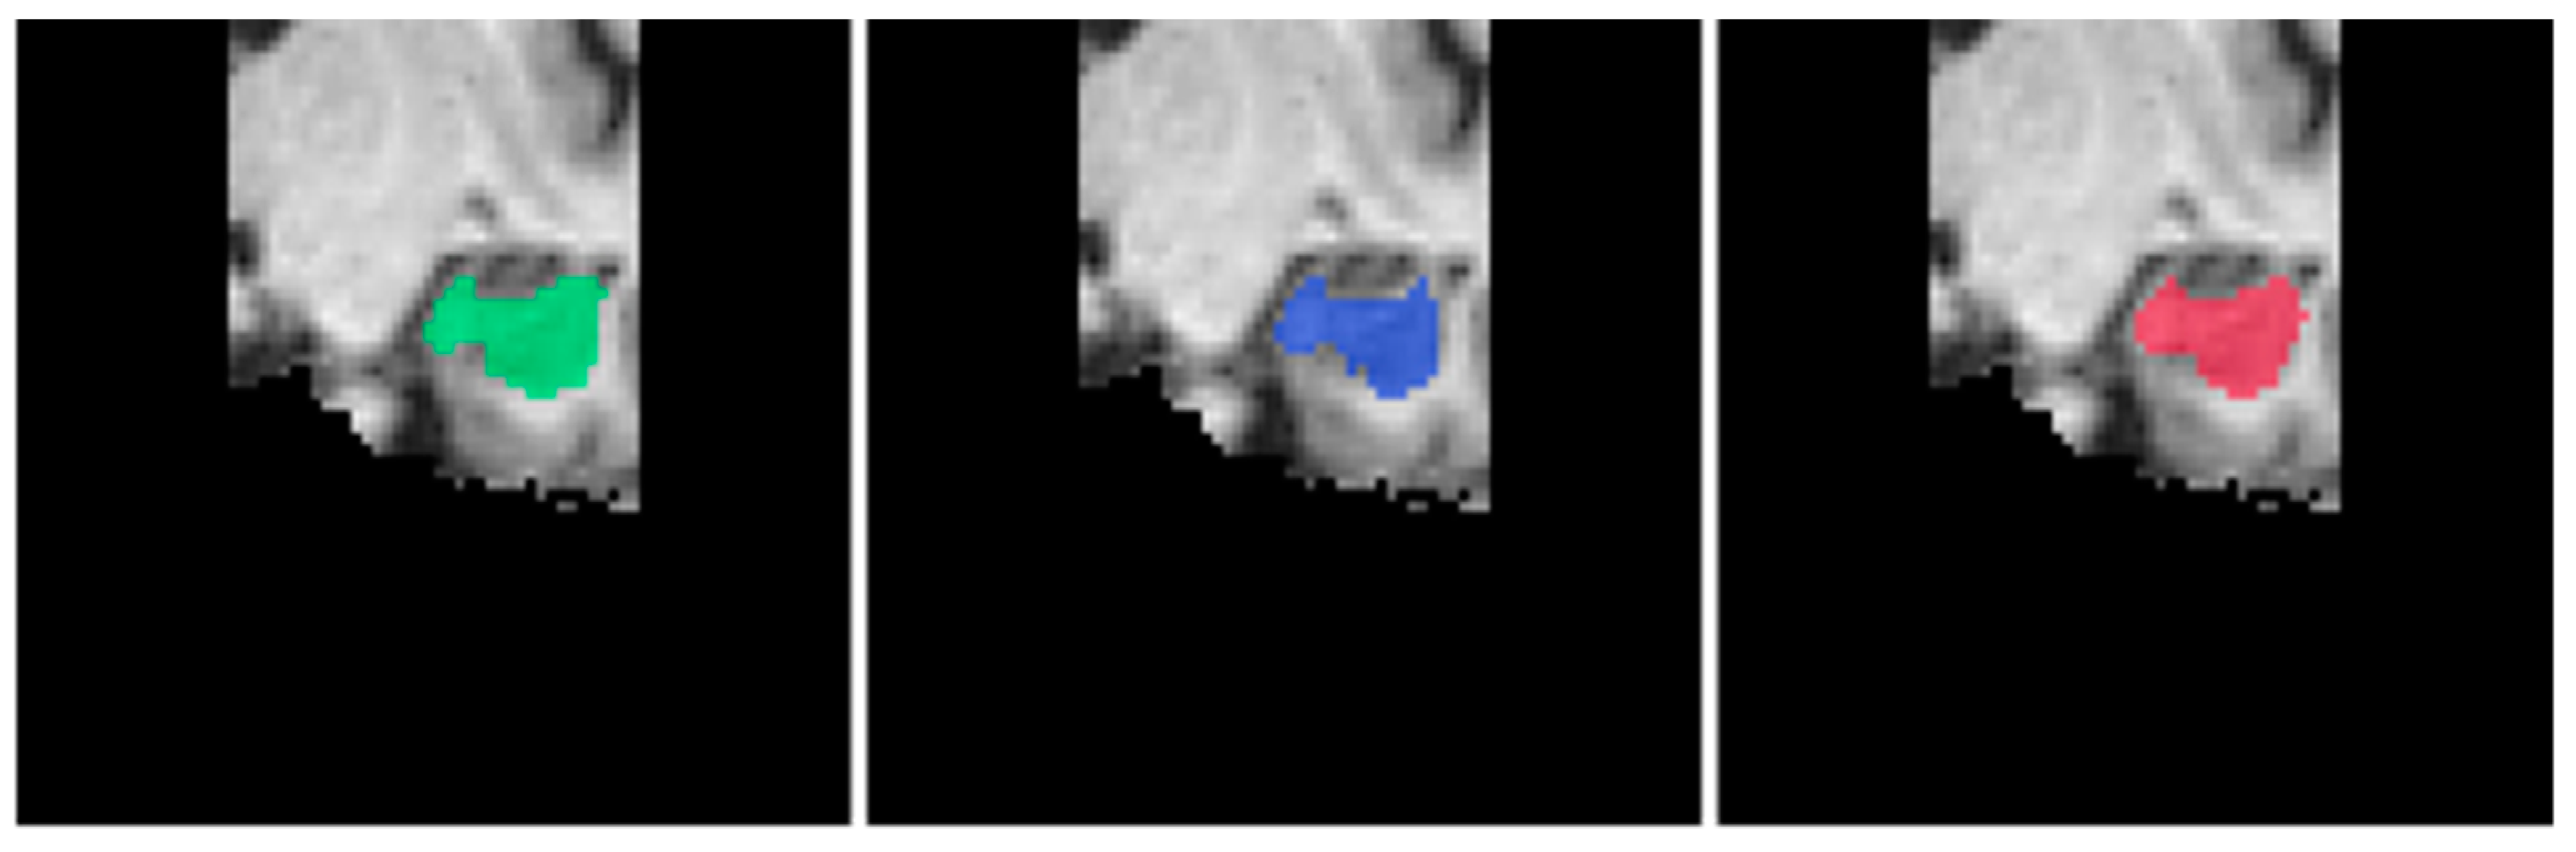

For the segmentation of the left hippocampus, we can see in Table 8 that EnsembleUSegNetL obtained higher DSC, precision, and recall scores as compared to 3D U-NetL. In terms of the hippocampus segmentation task, the higher precision and recall indicated that when compared to 3D U-NetL, EnsembleUSegNetL was less likely to falsely identify non-hippocampus voxels as part of the hippocampus and also was more capable of correctly detecting the actual hippocampus voxels. This meant that the EnsembleUSegNetL outperformed the 3D U-NetL when it came to hippocampus segmentation, which was reflected in the higher DSC score. An extracted coronal slice from the predicted segmentation masks and the ground truth hippocampus mask is shown in Figure 15 below.

Figure 15.

Sample coronal slices of predicted left hippocampus segmentation masks overlaid on the brain MRI in the order of ground truth (green), EnsembleUSegNetL (blue), and 3D U-NetL (red) from left to right.